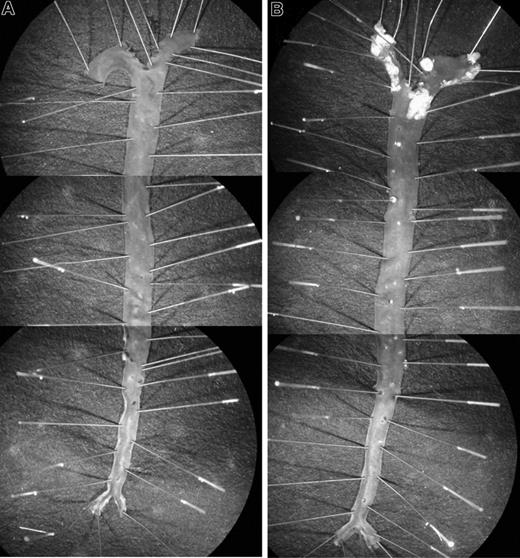

Experiments in which injured arterial segments from HCII−/− mice were incubated with tosyl-Gly-Pro-Arg-p-nitroanilide for 2 hours, then rinsed with buffer and incubated with fresh substrate, revealed that the rate of substrate hydrolysis was unchanged after rinsing (data not shown). This observation suggested that the thrombin remained active and stably associated with the vessel. To determine the location of thrombin activity in the vessel wall, we prepared frozen sections of carotid arteries harvested 1 hour after injury, incubated them with hirudin, and then detected the bound hirudin with an antibody. Hirudin binding was observed only in the injured vessels from HCII−/− mice (Figure 6), where it was located predominantly in the intima and media. Staining was less intense in the adventitia and in thrombi present in the lumen of the vessel.

Binding of hirudin to arterial sections. Frozen sections were prepared from carotid arteries of HCII−/− (A,C) or HCII+/+ (B,D) mice harvested 1 hour after injury. The sections were then incubated with hirudin in vitro, and bound hirudin was detected with sheep anti–hirudin IgG and a secondary antibody linked to peroxidase (C,D). Controls in which the primary antibody was omitted are shown (A,B). A thrombus is visible in the arterial lumen of the HCII−/− mouse. IEL indicates internal elastic lamina; EEL, external elastic lamina.